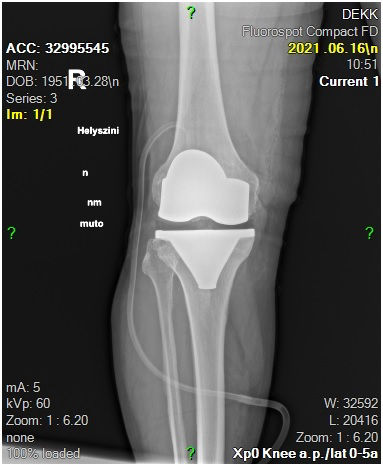

29 éves pályám során közel ezer térdprotézist és több mint kétezer csípőprotézist ültettem be. Az utóbbi években egyre több, nagy műszer igényű, összetett protézis revíziós műtétet végzek.